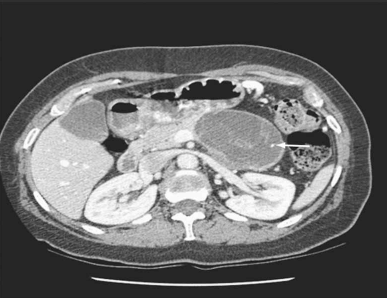

Mulher de 39 anos procurou atendimento por dor abdominal vaga, de fraca intensidade, há 4 meses. No exame físico, detectou-se uma massa abdominal de limites imprecisos e pouco dolorosa. Foi solicitada tomografia abdominal (imagem demonstrada). O exame histológico do material colhido por punção aspirativa com agulha fina revelou níveis baixos de amilase, presença de células ricas em mucina e estroma similar ao do ovário. O diagnóstico da paciente é: